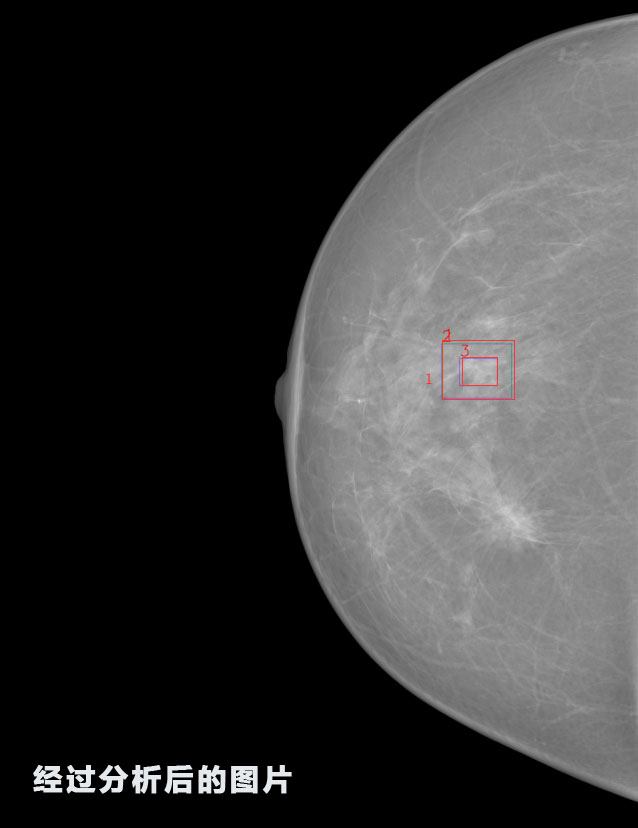

英特健康A(chǔ)I深度學(xué)習(xí)醫(yī)療圖像識(shí)別系統(tǒng)案例_乳腺

02.jpg

識(shí)別報(bào)告:

1.發(fā)現(xiàn)良性鈣化,可能性為19.88%---位置框指數(shù):[1796.0867 1359.8237 2058.1372 1582.5334]

2.發(fā)現(xiàn)惡意鈣化的可能性為15.18%---位置框指數(shù):[1789.4733 1365.9951 2063.7698 1576.0613]

3.發(fā)現(xiàn)惡意鈣化的可能性為12.45%---位于框指數(shù):[1859.3987 1422.3184 2006.5494 1528.2698]